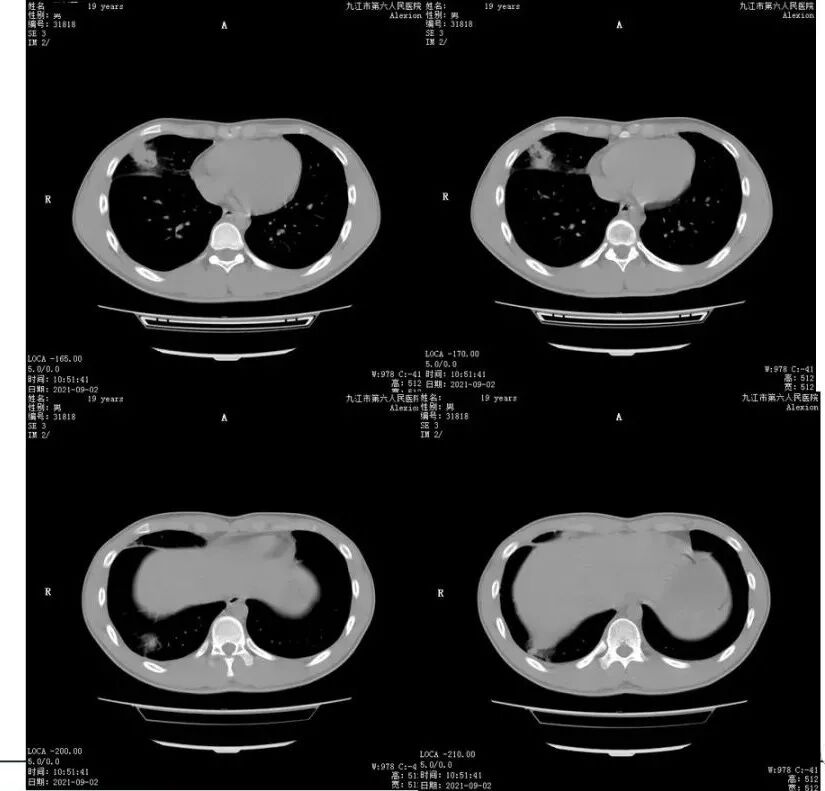

青年男性,右肺多发结节斑片状高密度影,周围较多晕,右上肺结节内见空洞形成。实验室检查嗜酸性粒细胞增高,考虑寄生虫感染,鉴别嗜酸性粒细胞肺炎

男,青少年,右肺中下叶斑片状高密度,密度不均,其内实性成分边缘平直,周围磨玻璃灶,边界模糊,化验嗜酸性粒细胞增高,炎症,考虑嗜酸性细胞性肺炎,

年轻男性,嗜酸性细胞明显升高,多发类结界病变,边界模糊,部分空洞,空洞内无气液平,似隧道,考虑肺寄生虫病,吸虫?

右肺多发实变影伴磨玻璃影,局部空洞改变,可疑轨道征

年轻男性,右肺中叶及下叶胸膜下多发结节,周围磨玻璃晕,部分似隧道,实验室嗜酸性粒细胞增高,考虑肺寄生虫,鉴别隐球菌

男,19岁,既往肺炎病史,CT示右肺多发实变影伴周围磨玻璃影,边界不清,中叶病变伴空洞,嗜酸性粒细胞增高,考虑寄生虫或嗜酸性细胞性肺炎可能

年轻男性,嗜酸性细胞明显升高,右肺多发斑片影,边界模糊,局部空洞,似隧道,考虑肺寄生虫病可能性大,真菌待排。

青少年,右肺中、下叶斑片状,结节状高密度,密度不均,内见扩张的支气管,周围磨玻璃影,嗜酸性粒细胞增高,考虑感染性病变,嗜酸性细胞性肺炎,寄生虫感染。

19岁,右肺多发片状及结节状高密度影,边缘模糊,见磨玻璃密度影,部分有空洞,呈薄壁,内壁规整,临近叶间胸膜增厚,考虑炎性肉芽肿性病变,化验嗜酸高,嗜酸性细胞性肺炎

胸部CT:右肺中下叶多发结节影、斑片影,周围模糊GGO,右中叶空洞结节,内壁光滑无气液平。右侧叶裂增厚。考虑:PC?寄生虫?鉴别药物、支气管中心肉芽肿病等。

胸肺部是LFD最主要的病变部位,MSCT在胸肺部病变检测中显示出一定优势,在不同阶段显示出不同病理特征。移行急性阶段为炎症、出血,后期形成囊肿、结节,病灶吸收后可出现钙化影,需与肺结核、支气管扩张、肺炎、肿瘤等鉴别。

LFD胸部X线基本表现为肺实质结节浸润、囊性病变、空洞性病变、纤维化钙化、胸膜增厚与积液、气胸、心包积液和横膈局限隆起。MSCT具有高分辨率、可全身扫描的特点,肺部CT异常征象主要有结节、磨玻璃影、囊变、虫蚀样变、“隧道”征、窦道形成、胸腔积液及胸膜增厚,其中“隧道”征为对该病的特征性发现,系由于吸虫在肺内迁移游走,对肺组织的慢性破坏而形成。